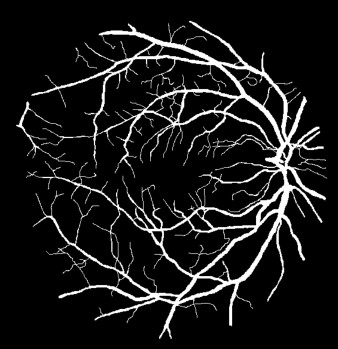

Semantic segmentation of blood vessels is an important task in medical image analysis, but its progress is often hindered by the scarcity of large annotated datasets and the poor generalization of models across different imaging modalities. A key aspect is the tendency of Convolutional Neural Networks (CNNs) to learn texture-based features, which limits their performance when applied to new domains with different visual characteristics. We hypothesize that leveraging geometric priors of vessel shapes, such as their tubular and branching nature, can lead to more robust and data-efficient models. To investigate this, we introduce VessShape, a methodology for generating large-scale 2D synthetic datasets designed to instill a shape bias in segmentation models. VessShape images contain procedurally generated tubular geometries combined with a wide variety of foreground and background textures, encouraging models to learn shape cues rather than textures. We demonstrate that a model pre-trained on VessShape images achieves strong few-shot segmentation performance on two real-world datasets from different domains, requiring only four to ten samples for fine-tuning. Furthermore, the model exhibits notable zero-shot capabilities, effectively segmenting vessels in unseen domains without any target-specific training. Our results indicate that pre-training with a strong shape bias can be an effective strategy to overcome data scarcity and improve model generalization in blood vessel segmentation.